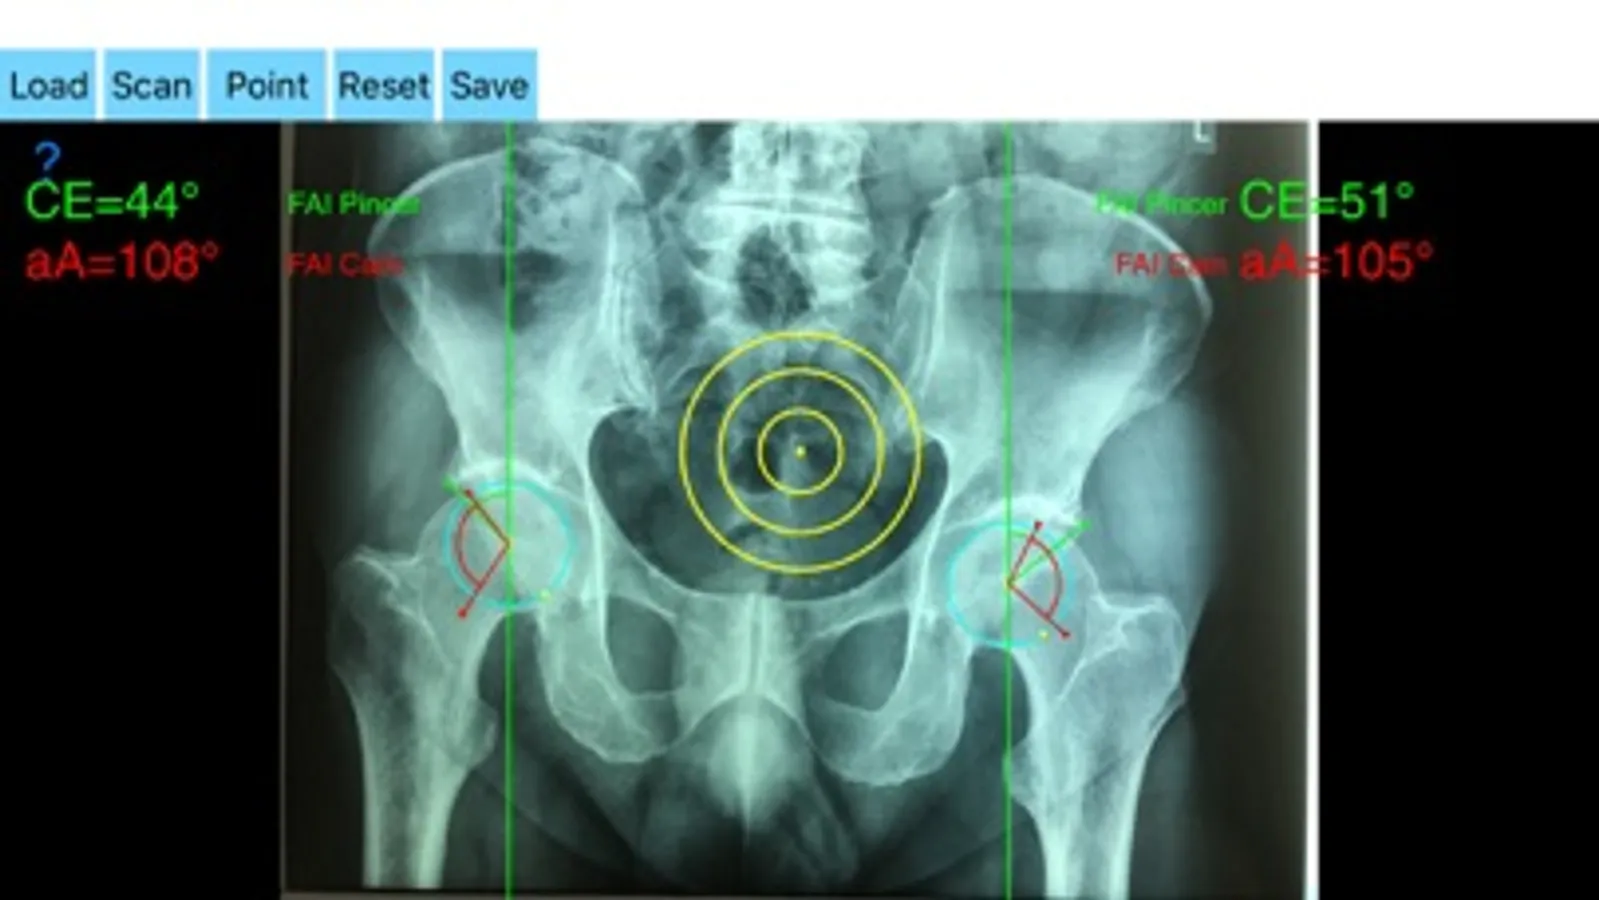

The drawn lines between points, allows app to estimate in radiographs, Center-Edge Angle (CE), α - angle (aA) and the anterior femoral offset ratio (AfOR). The measured values are compared with values from normal reference database. In case the measured angles are beyond the normal range, the hip is categorized as normal, dysplastic, borderline dysplastic hip and the type of femoroacetabular impingement (FAI) deformity namely cam type, pincer type or mixed is printed over the screen accordingly. Measures by the app are not affected by the X-ray projection.